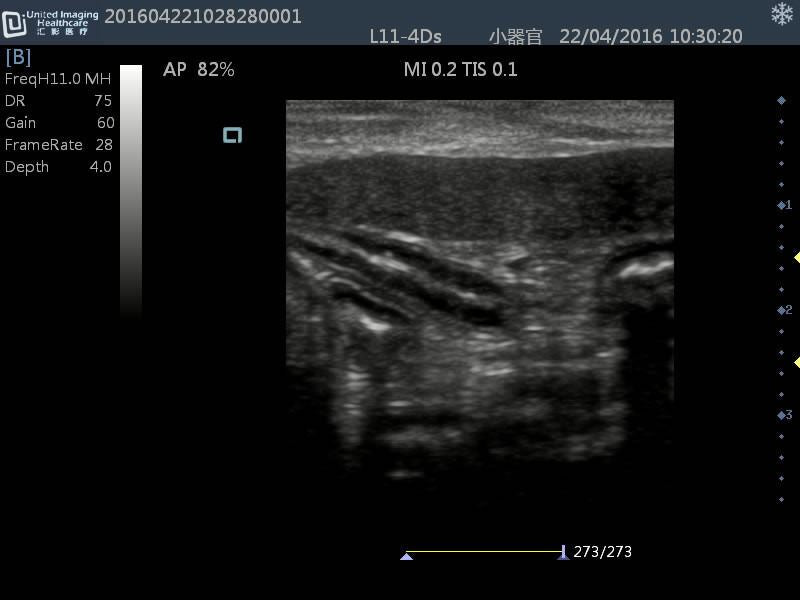

Linear(L40): L11-4Ds

- Application: Vascular, Small parts, Musculoskeletal, Carotid, Nerve, Orthopedic

- Number of element: 80

- Center frequency: 7.5MHz

- Working frequencies: 5 – 10MHz